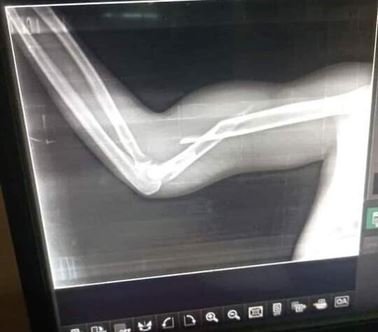

وبينت أن الحالات الثلاث وصلت إلى “مستشفى الحوادث” وتأكد إصابة شاب عمره 23 عام، نوع بكسور في أصابع اليد اليمنى، وشاب اخر عمره 24 عام أصيب بكسر في عضد اليد اليمنى، بينما أصيب شاب ثالث يبلغ من العمر 22عام بكسر في اليد اليمنى.

بينما سجلت في مواكب الخرطوم أيضا حالات مماثلة وصلتوفي مجملها إلى 15 حالة حتى الآن، وقعت كل هذه الإصابات دون حدوث أي إشتباك مباشر ودون أن تترك اثر خارجي ظاهر في الجلد.